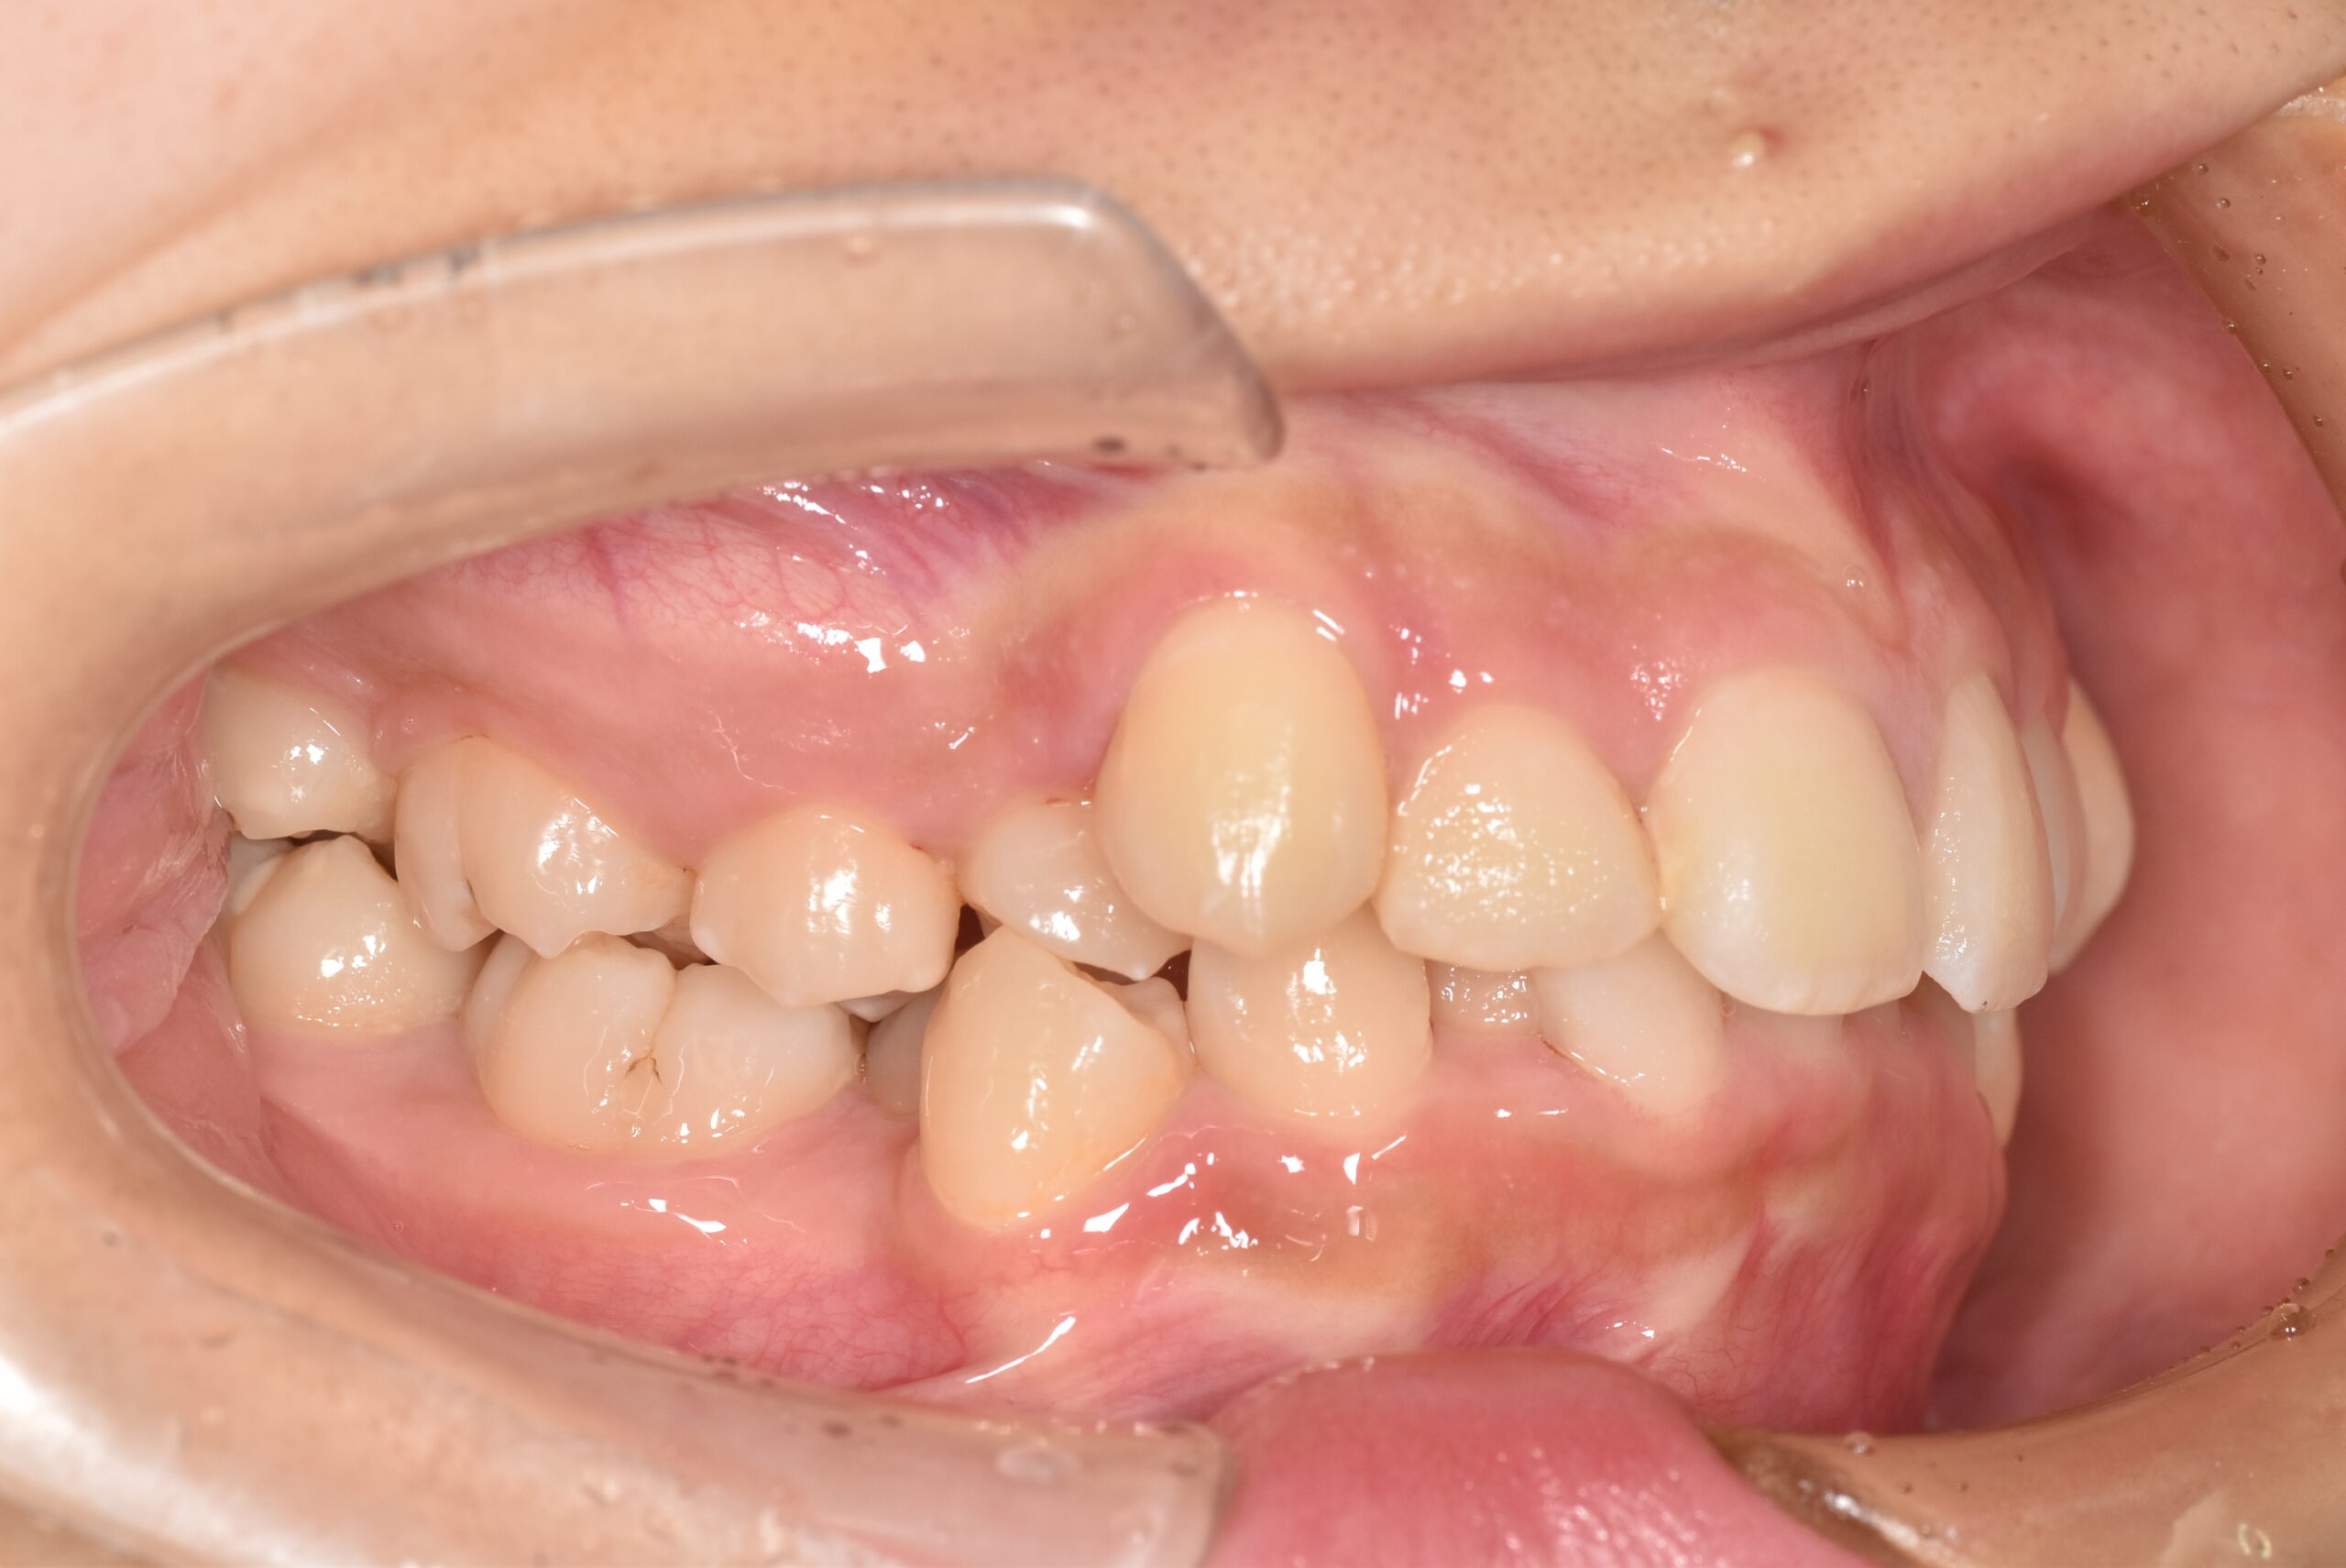

BEFORE

| 年齢 | 19歳 |

|---|---|

| 主訴 | ガタガタが気になる |

| 症状 | 過蓋咬合を伴う叢生症例 |

| 治療内容 | 過蓋咬合を伴う叢生症例と診断し上下顎両側第一小臼歯の抜歯を行い、マルチブラケット装置を用いて治療を行いました。上顎は裏側の矯正装置、下顎は表側の矯正装置で治療を行いました。ハーフリンガル矯正治療。 |

| 抜歯部位 | 上下顎両側第一小臼歯 |

| 治療期間 | 3年 |

| 費用(税込) | 1,045,000(税込)別途処置料 |

| 治療のリスク | 虫歯、歯周病の悪化、歯肉退縮、歯根吸収、顎関節症の悪化、後戻り |